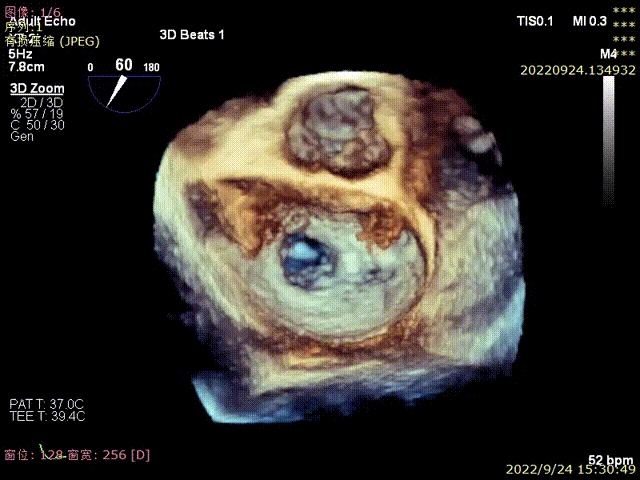

图3,由于患者反流位置位于3区偏交界,在MultiVue模式指导下进行操作

图4,夹子植入后消除P3区反流,残余P3偏P2区反流